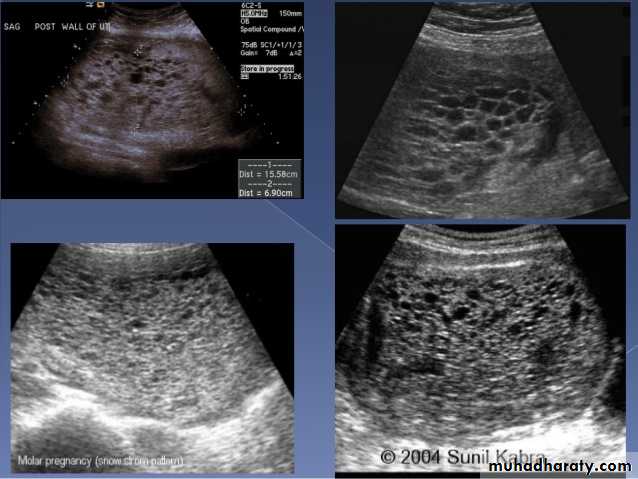

Molar pregnancy

Gestational trophoblastic disease (GTD) results from abnormal proliferation of trophoblastic tissue, and encompasses a wide spectrum of diseases, including:

hydatidiform mole

complete mole

partial mole

invasive mole

Chorio carcinoma (gestational choriocarcinoma)

Radiographic features

Ultrasound

enlarged uterus

classic sonographic appearance is that of a solid collection of echoes with numerous small (3-10 mm) anechoic spaces (snowstorm appearance).

the molar tissue demonstrates the punch of grapes sign which represents hydropic swelling of trophoblastic villi.